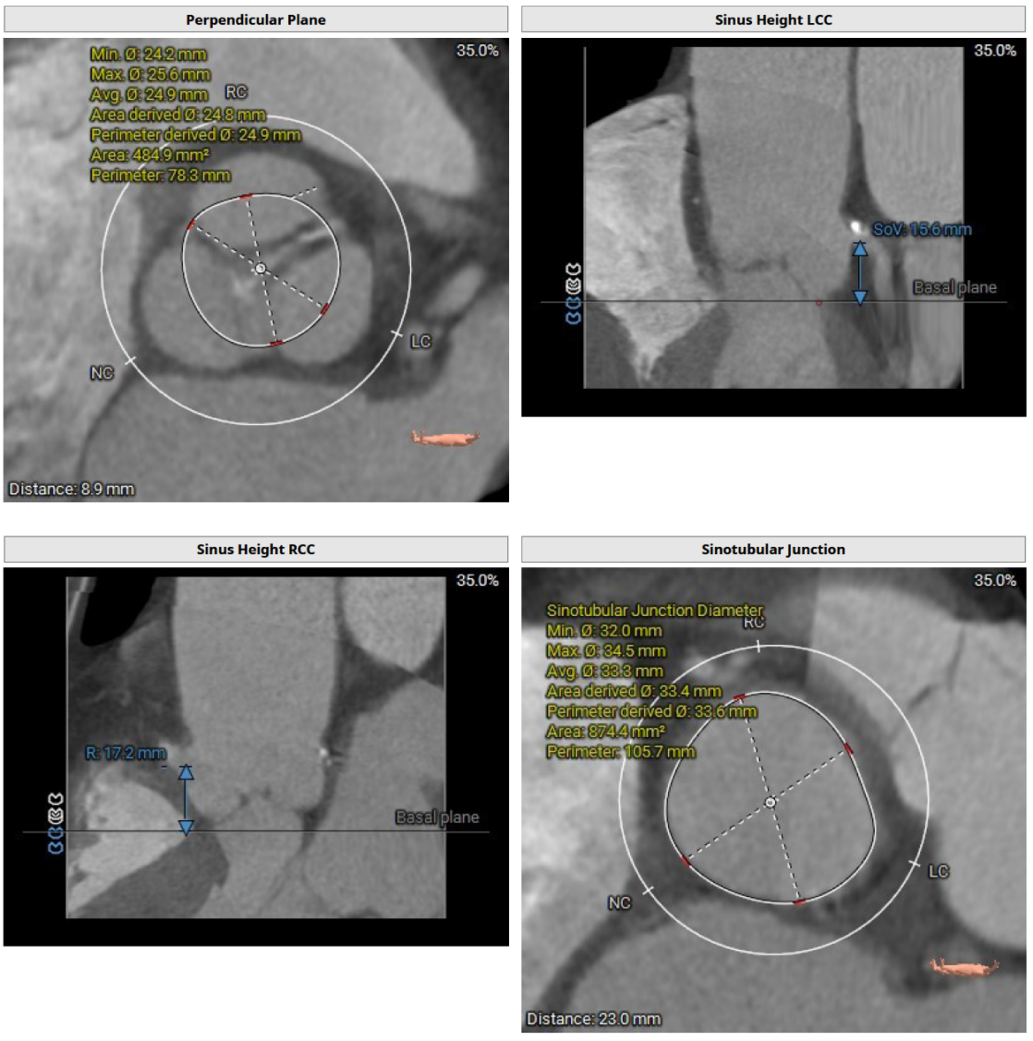

CT评估及手术策略

患者为三叶式主动脉瓣,重度反流。瓣叶交界轻度钙化。瓣环周长76.3 mm,平均径24.3 mm。LVOT周长77.3 mm,平均径24.0 mm。瓣上3.8 mm、5.0 mm、8.9 mm处空间为76.8 mm、82.8 mm、78.3 mm。STJ 周长105.7 mm,高度23 mm,升主周长126.5 mm 增宽、瓦氏窦大。综上所述建议TAV 27 瓣膜。左右冠高度15.6 mm、17.2 mm相对瓣膜支架可,冠脉风险低。股动脉入路血管轻度迂曲,双侧股动脉分叉高度可。腹主动脉、双侧髂总动脉散在钙化斑块。右侧股动脉平均内径最小6.3mm,左侧股动脉平均内径最小5.8mm,建议选择右侧股动脉为主入路。